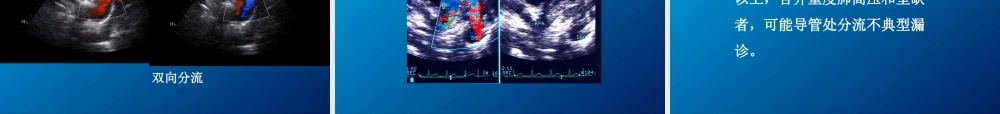

动脉导管未闭(Patentductusarteriosus,PDA)发生率约占先天性心脏病的10%~15%,仅次于房间隔缺损或室间隔缺损,可与其它畸形合并存在。教学目的与要求PDA超声表现及诊断要点重点PDA合并肺动脉高压的诊断难点PDA常合并的畸形了解一、病理解剖PDA位于主动脉峡部的小弯侧与主肺动脉分叉左支处。按其形态一般分三型:①管型;②漏斗型;③窗型(缺损型);④瘤型;后两型少见。PDA直径0.5cm左右最多见。二、血流动力学改变及临床大动脉水平分流,无肺高压时,降主动脉血流通过PDA进入肺动脉,呈连续性分流;肺循环及左心容量负荷过重;后期肺动脉压增高,分流特征发生改变。胸骨左缘2肋间连续性杂音三、超声心动图检查要点首选胸骨旁主动脉根部短轴观,显示肺动脉长轴及分支,在左肺动脉根部与降主动脉之间寻找未闭导管;胸骨上窝主动脉弓长轴切面显示主肺动脉远侧端短轴及主动脉峡部,在左锁骨下动脉开口的对侧寻找。四、超声心动图表现左房、左室增大左心室容量负荷过重表现PDA直接征象(漏斗型):PDA在左、右动脉分叉处或左肺动脉根部与后方的降主动脉相通,PDA征象(管型):此型最多见肺动脉及分支扩大PDA彩色多普勒血流动态(CDFI)降主动脉血流经导管进入肺动脉的红色或五彩镶嵌花色血流信号,通常分流方向位于肺动脉外侧上行左向右分流静态图小导管CDFI动态(易漏诊)小导管的诊断依赖CDFI频谱多普勒超声心动图特征:动脉导管开口处显示连续性或全舒张期的湍流频谱,速度多数在3-4m/s典型PDAPDA合并肺高压(易漏诊)PDA合并肺高压双向分流PDA并心内膜炎,肺动脉大量赘生物五、临床诊断价值单纯PDA检出率达98%以上,合并重度肺高压和室缺者,可能导管处分流不典型漏诊。PDA超声诊断要点•动脉分叉处或左肺动脉根部与后方的降主动脉相通的管道;•降主动脉血流经导管进入肺动脉的上行血流显像;•动脉导管开口处连续性湍流频谱,速度多达3-4m/s;•2~3mm小导管和重度肺高压容易漏诊。小结小结先天性主动脉狭窄(aorticvalvularstenosis,AS)是指从左室流出道至升主动脉之间任何部位出现的梗阻,约占先天性心脏病的3%~6%。先天性主动脉瓣狭窄是其中最常见的畸形。主动脉狭窄教学目的与要求主动脉狭窄的超声表现及诊断要点重点主动脉狭窄合并存在的其他畸形的诊断难点主动脉弓离断、主动脉缩窄的超声表现了解病理解剖:分为主动脉瓣狭窄、主动脉瓣下狭窄和主动脉瓣上狭窄。主动脉瓣狭窄多为二叶瓣畸形,瓣膜增厚开口狭窄;主动脉瓣下狭窄多...